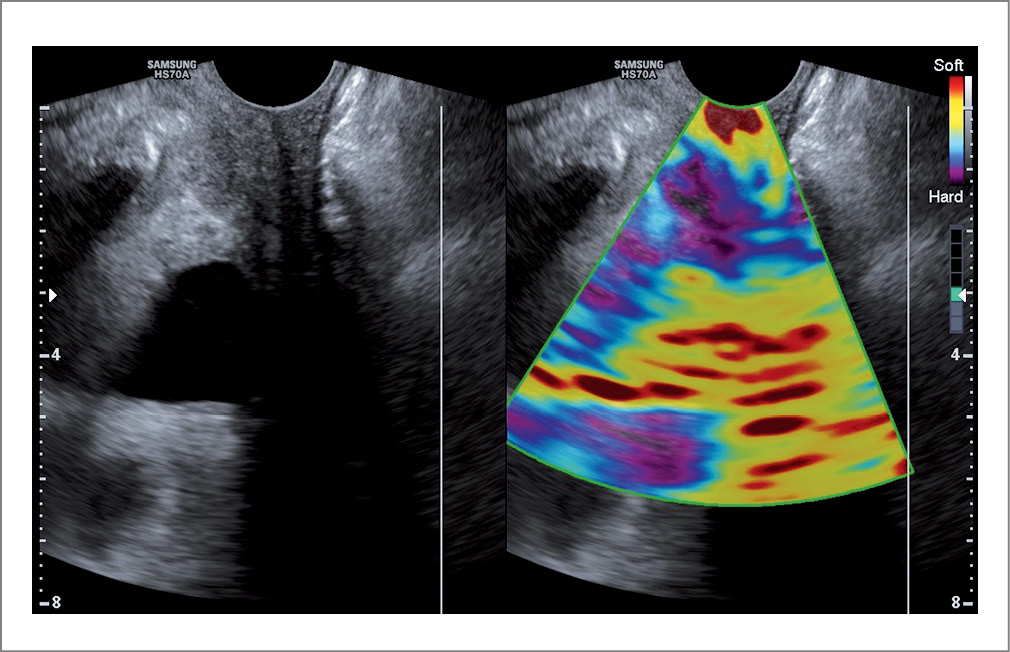

При проведении ультразвукового исследования с эластографией после операции и проводимой терапии в 1 и 2-й группах преимущественно отмечалось повышение эластичности тканей влагалища. На эластограмме ткани стенок влагалища картировались зеленым цветом с участками синего (рис. 3). Коэффициент деформации увеличился относительно показателей до операции. Через 3 мес после операции в 3-й группе по-прежнему преобладала средняя и низкая степени эластичности тканей стенок влагалища и более низкие показатели коэффициента деформации относительно 1 и 2-й групп (рис. 4).

Рис. 4. Ультразвуковое исследование с эластографией через 3 мес после операции. / Fig. 4. Ultrasound with elastography 3 months after surgery.